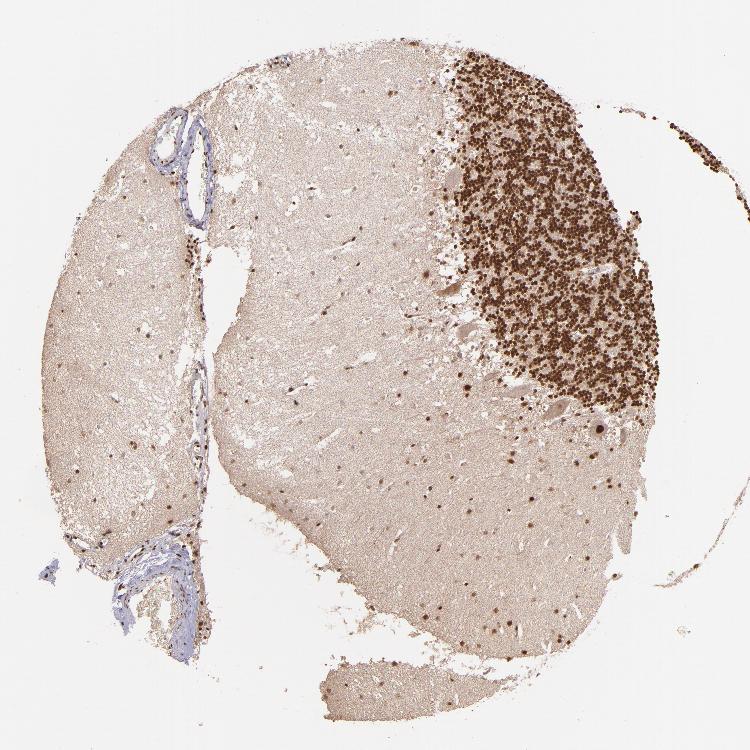

CEREBELLUM - Antibody stainingi

Antibody staining in the annotated cell types in the current human tissue is reported as not detected, low, medium, or high, based on conventional immunohistochemistry profiling in selected tissues. This score is based on the combination of the staining intensity and fraction of stained cells.

Each image is clickable and will lead to virtual microscopy that enables deeper exploration of all samples and also displays staining intensity scores, fraction scores and subcellular localization as well as patient and tissue information for each sample.

Antibody HPA001880

Purkinje cells High

Cells in granular layer High

Cells in molecular layer High